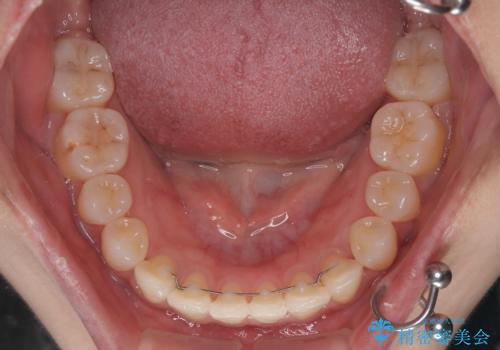

- 矯正装置

- メタルブラケット

- 左上の前歯のがたつきを主訴に来院された患者様です。

上顎歯列が下顎の歯列に対して狭小であり、一部下顎の奥歯が上顎よりも外側に位置している状態でした。

上顎の歯列を拡大しスペースを設け、さらに左上の小臼歯を一本抜歯し左上の八重歯を歯列内に入れ整えていくことにしました。